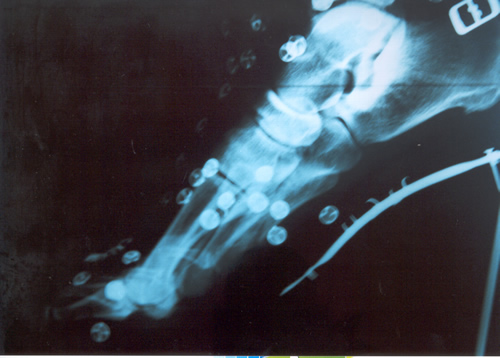

Sin embargo, puede ocurrir que luego de la inmovilización sin apoyo del pié lesionado, y que el informe de las imágenes radiográficas y tomográficas, no demuestren un callo aceptable para el comienzo de la rehabilitación kinesiológica, está la posibilidad de la resolución quirúrgica.

También ésta, presenta dos alternativas. O bien disconforme con la imagen que arrojan los estudios se indica osteosíntesis de aquella mediante un tornillo ó bien si intentan con rehabilitación kinesiológica post inmovilización, recuperarlo a pesar de un callo endeble, puede ocurrir que no se logre lo deseado.

En este caso, si el jugador en varios intentos de probar en el campo de juego siente dolores o se genera dolor parecido al inicial luego de caídas repetidas, estaremos en presencia de un déficit de consolidación por retardo de la misma ó peor aún, seudoartrosis ó falsa articulación ó movimiento indeseable en el foco de la fractura que impide la total recomposición de la misma.

En este estadío es cuando no cabe duda que la indicación es la operación . Personalmente nosotros hemos realizado osteosíntesis con tornillo junto a injerto óseo en el lugar lesionado que es extraído de la cresta ilíaca de la pelvis. Elemento óseo éste con gran irrigación sanguínea que viene a alimentar el déficit del hueso metatarsiano. Siempre utilizamos inmovilización enyesada por 45 días. Habrá quien utilice ortesis y ello depende la casuística de cada cirujano. Pero esto ya es tema para otro artículo.